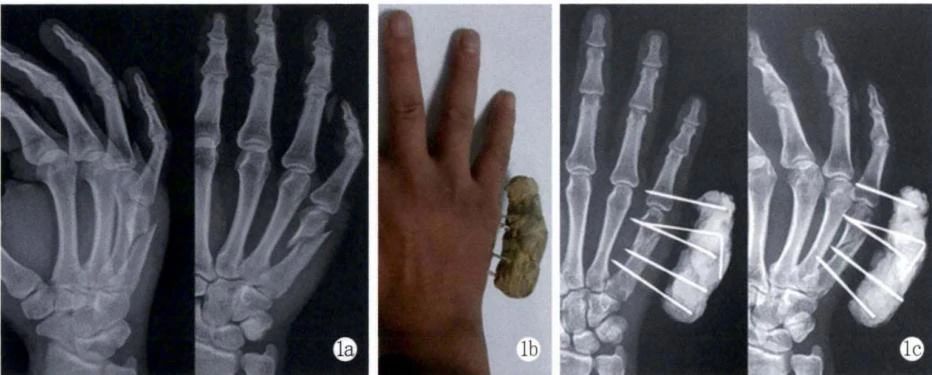

На снимке выше представлен перелом шейки пятой пястной кости правой руки, подвергшийся закрытой репозиции и чрескожной фиксации самодельным внешним фиксатором из костного цемента.

1a: Рентгенограмма до операции: перелом шейки пятой пястной кости, очевидный угол и смещение ладонной кости, а также шейно-диафизарный угол 52°; 1б: Послеоперационный вид;

1c: Послеоперационная рентгенограмма показывает, что перелом хорошо сросся;

1e, 1f: Функция была хорошей в течение шести месяцев после операции, TAM 88°. (из ссылки 12)